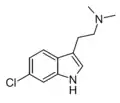

| 5-Chloro-DMT | artificial | 5-Cl | CH3 | CH3 | 5-chloro-N,N-dimethyltryptamine | 22120-32-7 |

| ST-1936 | artificial | 2-CH3, 5-Cl | CH3 | CH3 | 2-(2-methyl-5-chloro-1H-indol-3-yl)-N,N-dimethylethanamine | 1210-81-7 |